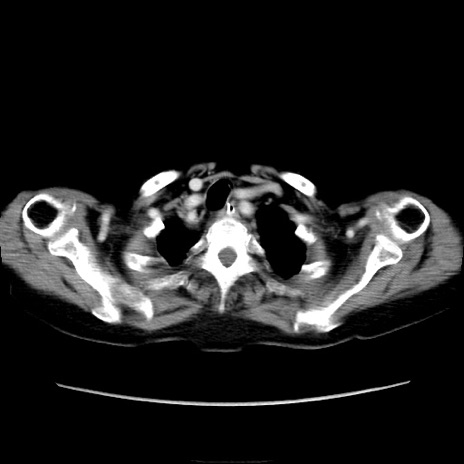

症例40(横断像)

【症例】90歳代女性

【主訴】腹痛・嘔吐

【現病歴】 食欲低下、嘔吐があり昨日他院受診。肺炎と診断され入院となる。入院後より腹部全体に圧痛あり。胃管留置され経過みていたが、症状持続するため、

当院転院となる。

【既往歴】胸椎圧迫骨折、胆石症

【身体所見】腹部:中央に激痛あり、圧痛あり、反跳痛不明

【データ】WBC 17100、CRP 18.82

横断像